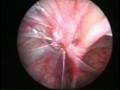

Torsion Testis (Pre and Per operative photo)

Of the many causes of acute scrotum, the most common and important is Torsion of Testis. The testis is supplied by a single blood vessel and any torsion on this vessel may impede the blood supply to the testis. If urgent medical attention and intervention is not done, this may result in testicular gangrene and orchidectomy ( removal of the dead testis) may be needed.

The commonly misleading history given by the parents is that the child may have had a trivial trauma or an insect bite. However, for the clinician the golden rule should be ‘Any acute scrotum is testicular torsion unless proved otherwise’. Investigations like ultrasound and color doppler may be done to help in the diagnosis. However, in the event of any doubt, it is safest to do a surgical exploration of the scrotum. The other uncommon causes of acute scrotum are acute epidydymo orchitis, scrotal abscess, idiopathic scrotal oedema and torsion of appendix of the testis. ●